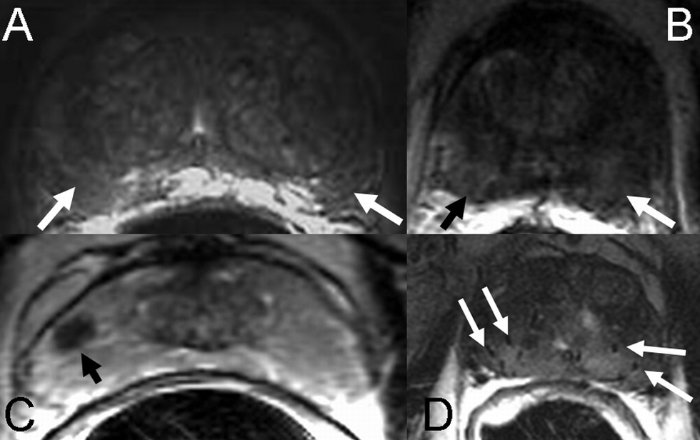

El estudio de la próstata mediante Resonancia Magnética Nuclear (RMN) requiere un moderno equipo de RMN (multiprámetrica) y un radiólogo experto en esta técnica.

En hombres con sospecha de cáncer de próstata se realiza un estudio con 3 secuencias: planos en T2, difusión axial y estudio de perfusión.

La RMN es muy fiable para pacientes que ya han sufrido biopsia de próstata, el PSA sigue subiendo y se les plantea la realización de una nueva biopsia. En estos casos la RMN nos permite valorar si existen focos-zonas sugestivas de cáncer o si la próstata es normal. Si la RMN nos identifica zonas sugestivas de cáncer debemos realizar biopsias dirigidas en esta zona sospechosa que nos marca la RMN. Si la RMN es normal, no hay zonas sospechosas, puede evitarse la biopsia.

Actualmente, la RMN también es muy útil en pacientes con PSA elevado y Tacto Rectal Normal, en los que se plantea la realización de una 1ª biopsia por PSA alto. En estos casos, la presencia de zonas sospechosas de cáncer en la RMN nos indicará la necesidad de realizar biopsia de próstata y si el estudio con RMN es normal, sin focos sospechosos, podría evitarse la biopsia.